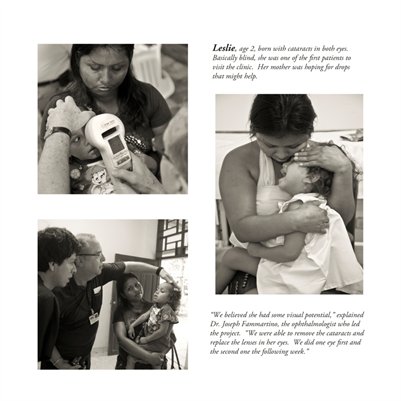

Darkness into the Light. In 2012, The Amazon Project gave eye care to nearly 6000 patients within a 200 kilometer radius of their base in Leticia, Colombia.